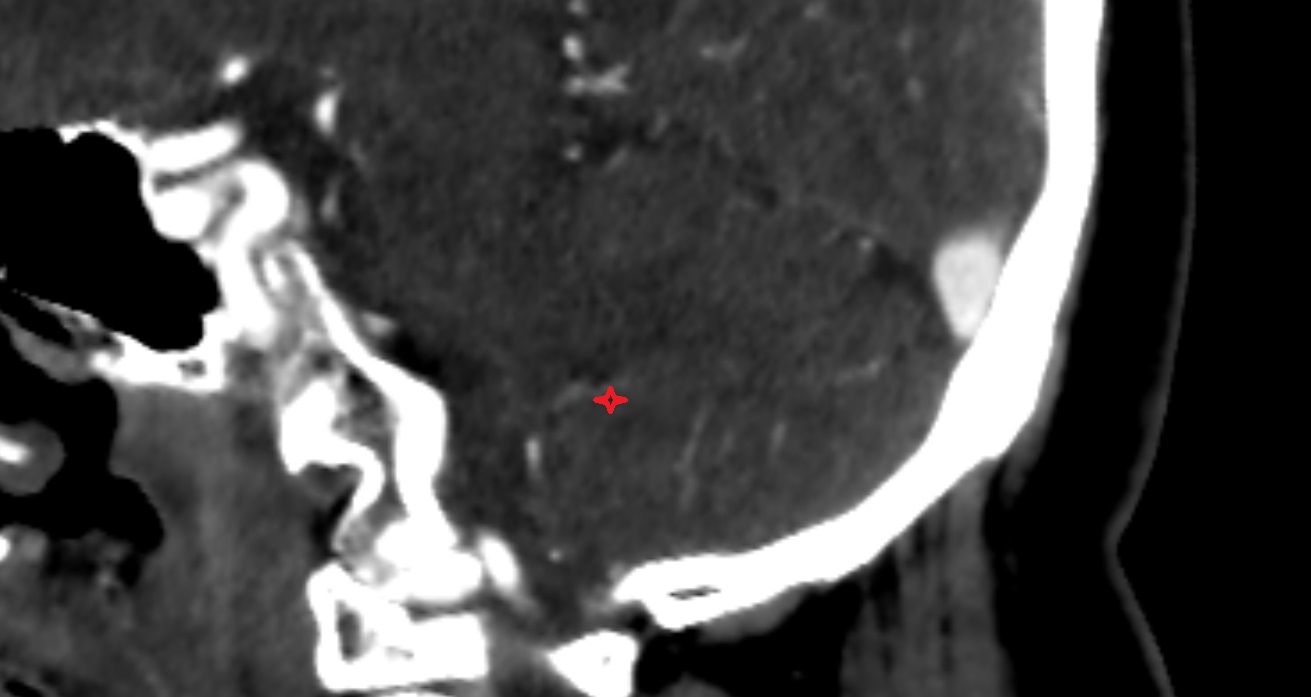

- Cerebellum

- Clivus

- Dorsal root of spinal nerve